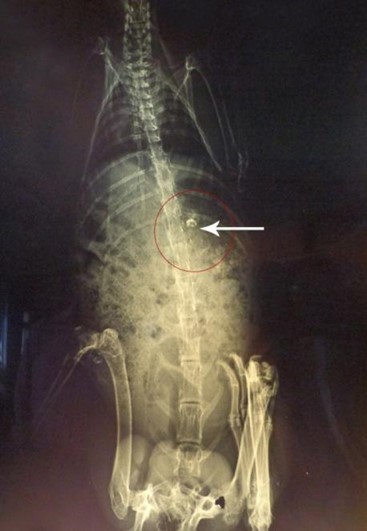

X-ray studies revealed that the microspheres remained in the stomach for the first 2h as shown in fig. (7). Microspheres get released from the capsule shell by dissolving the gelatin shell and distributed in the small intestine as observed in the fig. (8).

Since the particles are small, and the amount of radio-opaque material is also less, the amount of microspheres visible by X-rays is also minimal. Microspheres are visible at 4th h in the small intestine as observed in fig.(8), and some are also seen in the X-ray image taken at the 8th h in the large intestinal region [22]. X-ray image at 10th h indicates the presence of microspheres in the colonic region as seen in fig.(10). The observations were confirmed by a veterinary surgeon. It can be concluded that the formulation is able to target colonic region effectively.

Fig. 9: X-ray image after 8 h